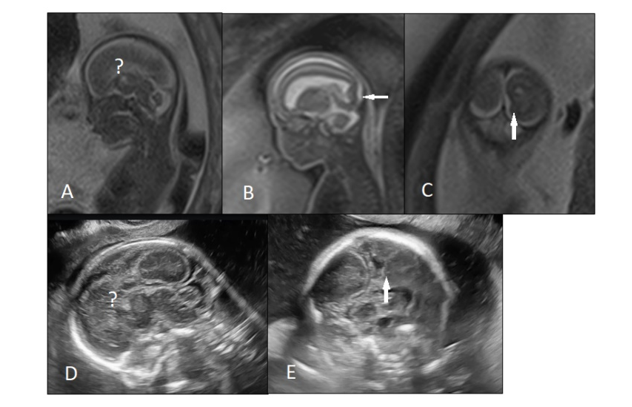

In subgroup a, US, NSG, and MRI findings were concordant; however, in subgroups b-d, MRI/NSG findings were discordant with US findings. Cases of MRI-NSG discordance were also outlined in the same manner and were subdivided into two groups: (1) concordance between NSG and MRI; (2) and NSG-MRI discordance (Figure 2).

Figure 2. A 34 weeks fetus with megacisternamagna was referred for fetal MRI. A, B) T2-weighted MRI showed megacisternamagna and unilateral periventricular heterotopia (arrow). C) Neurosonography at the same day of MRI found similar periventricular heterotopia (arrows).

Among all enrolled cases, NSG-MRI discordance was found in 22.9% (32) of fetuses, all showing additional findings in MRI, while none showed additional or contradicting findings on NSG (Figure 2). Table 3 describes the NSG findings in each of these 32 cases and shows any additional MRI features that were not visible on NSG. Interestingly, 4 fetuses had normal brains in NSG exams but were diagnosed with IVH/GMH in MRI. MRI was superior to NSG to detect intracranial hemorrhage and cortical malformations and offered a more accurate estimation of the extension of cortical malformation. Table 3 also outlines the final delivery outcome and duration of follow-up for each of these cases.